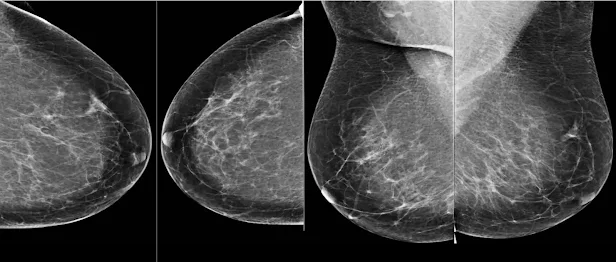

Маммограмм бүр дөрвөн зурагтай байдаг - хөх тус бүрээс хоёр өөр өнцгөөс.

Хөхний хорт хавдар нь эмэгтэйчүүдийн дунд нас баралтын хоёр дахь тэргүүлэх шалтгаан бөгөөд эрт илрүүлж эмчилбэл амьдрах магадлал өндөр байдгийг судалгаагаар тогтоосон. Иймээс олон улс хөхний хорт хавдрын скринингийн хөтөлбөр хэрэгжүүлж, өвчнийг эрт илрүүлэхийг зорьж байна. Гэвч маммограм (хөхний рентген зураг)-ыг тайлбарлахад эмч мэргэжилтнүүдийн оношилгооны нарийвчлал хэлбэлзэлтэй байсаар байна. Үүнийг шийдвэрлэхийн тулд Google Health, Cancer Research UK Imperial Centre, Northwestern University, Royal Surrey County Hospital хамтран AI-д суурилсан оношилгооны систем хөгжүүлсэн бөгөөд уг систем нь АНУ, Их Британийн эмч мэргэжилтнүүдийг давж гарсан болохыг Nature сэтгүүлд нийтэлсэн судалгаа баталжээ.